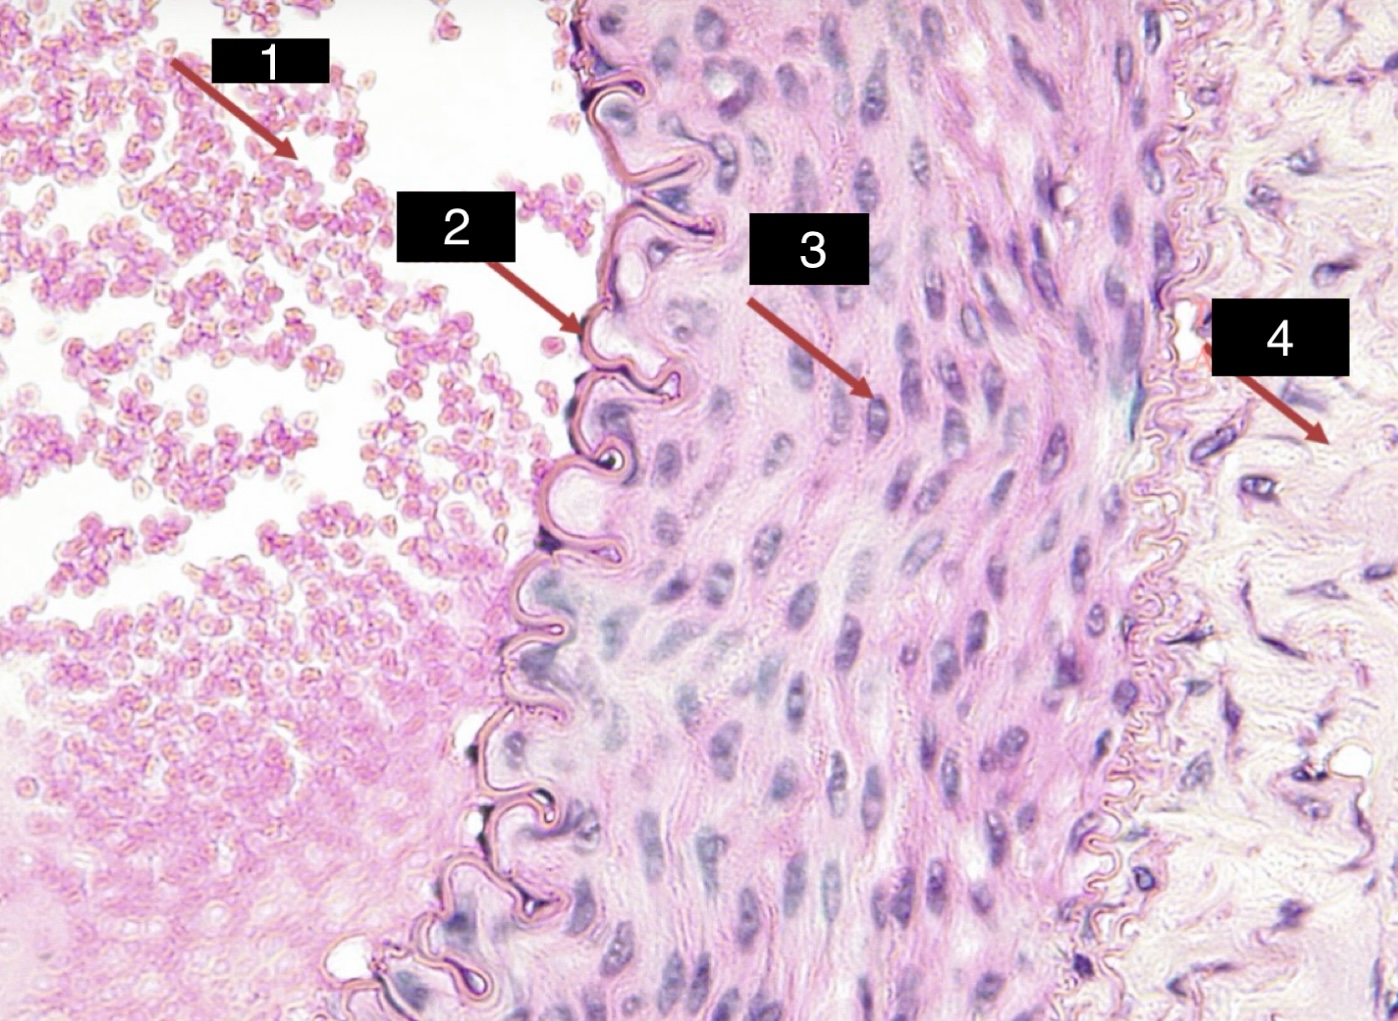

artery slide

artery - tunica intima

2

artery - tunica media

3

artery - tunica adventitia

4